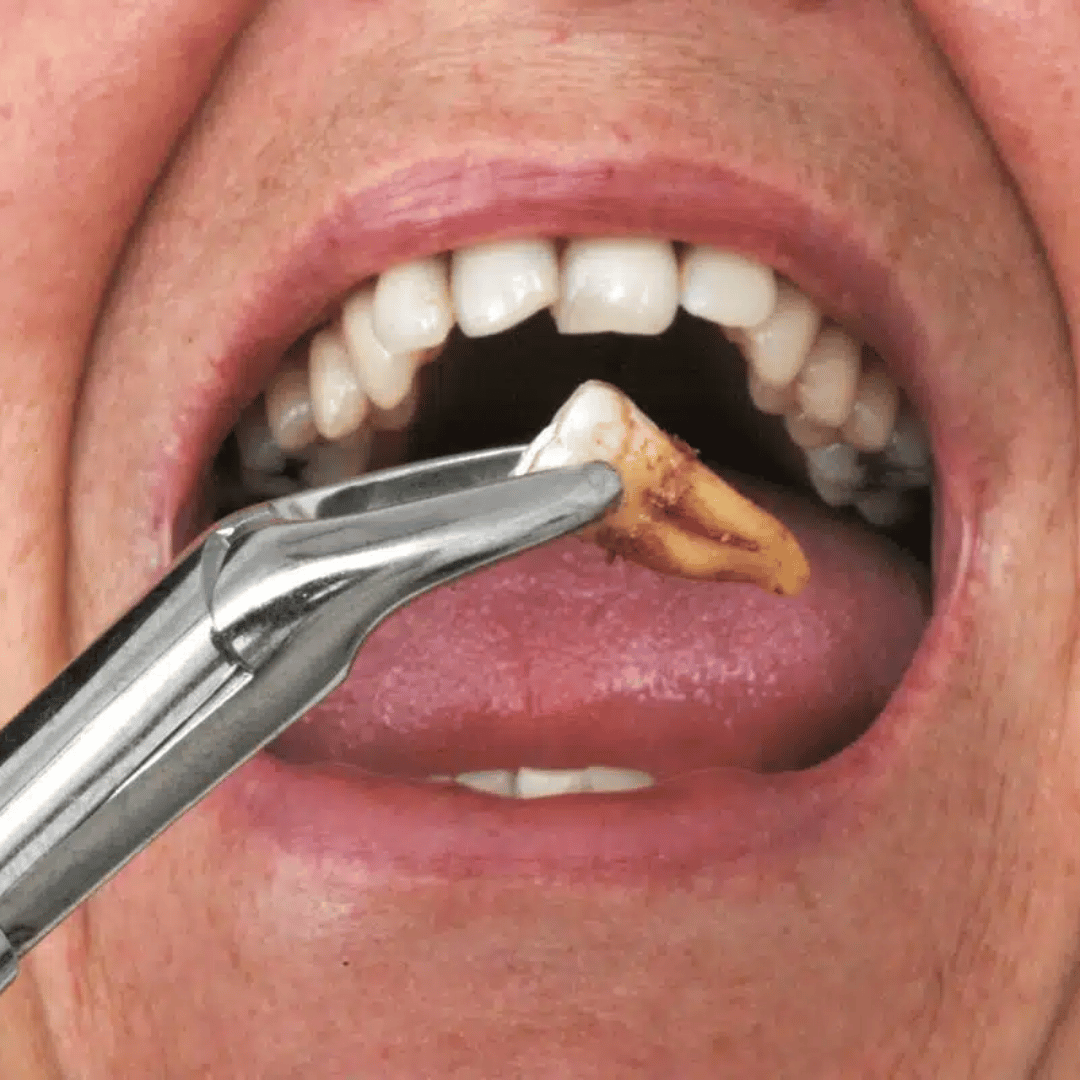

Full Mouth Rehab Services

Complete repair for damaged or worn teeth.